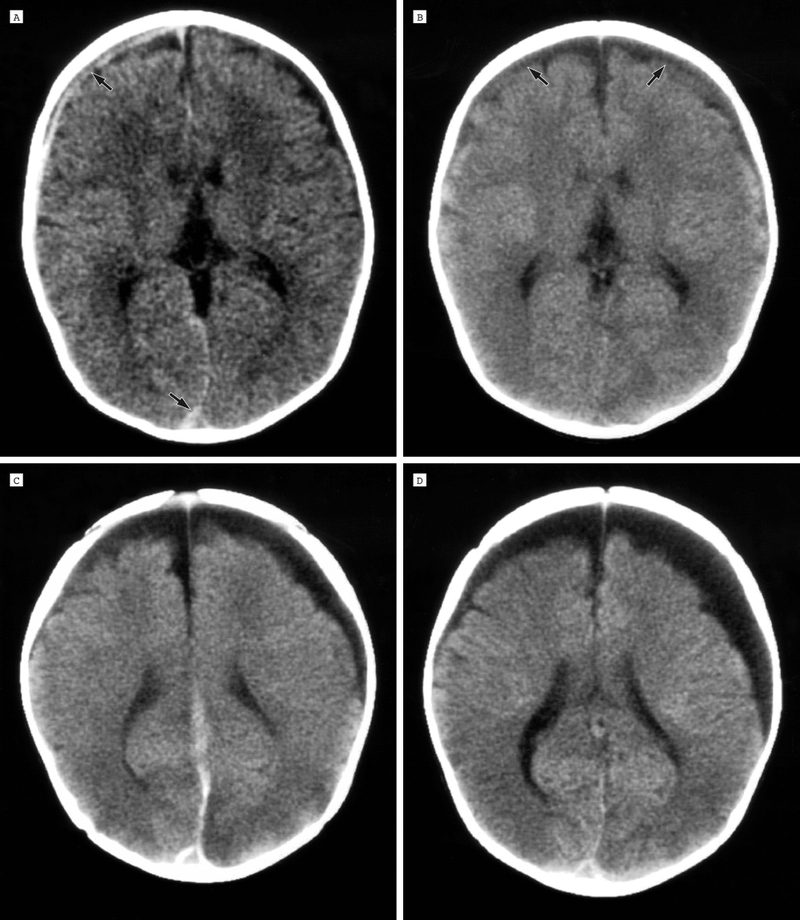

Để hiểu rõ hơn về u nang màng nhện ở thai nhi, trước tiên ta cần biết thế nào là nang màng nhện? Về mặt mô học, nang màng nhện là một khối choáng chỗ lành tính chứa đầy dịch não tủy tại hệ thần kinh trung ương. Hấu hết các trường hợp là tổn thương lành tính, có thể nằm ở nội sọ (đa số nằm ở vị trí trên lều), tủy sống hoặc quanh dây thần kinh. Thông thường khoảng 50% các nang màng nhện xuất hiện ở hố sọ giữa, 11% là ở góc cầu - tiểu não, 8-9% ở vùng yên, ống sống.

Nang màng nhện ở thai nhi là một nang đơn độc, chưa nước, dịch não tủy và thường xuất hiện ở não hoặc tủy sống. Hầu hết các trường hợp là dạng tổn thương lành tính, hiếm khi liên quan đến các bất thường nhiễm thể thường gặp trong lúc mang thai như NST 13, 18, 21 hay bất thường về não khác, chỉ có 2-5% có liên quan đến chấn thương hoặc nhiễm trùng (nang thứ phát). Nang màng nhện ở thai nhi được chia ra giới hạn bởi 2 lớp là: Màng trong và màng ngoài. Các lớp màng này có thể được tạo ra bởi tế bào thần kinh đệm, tế bào màng ống nội tủy hay lá của tế bào màng nhện.